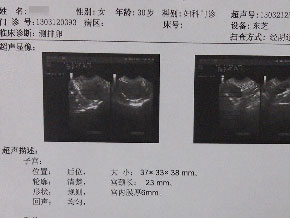

查输卵管

查输卵管 查内分泌

查内分泌 查免疫

查免疫 查卵巢

查卵巢 查子宫

查子宫 查脑垂体

查脑垂体